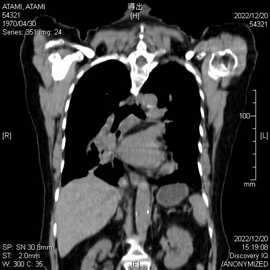

通常のCT画像